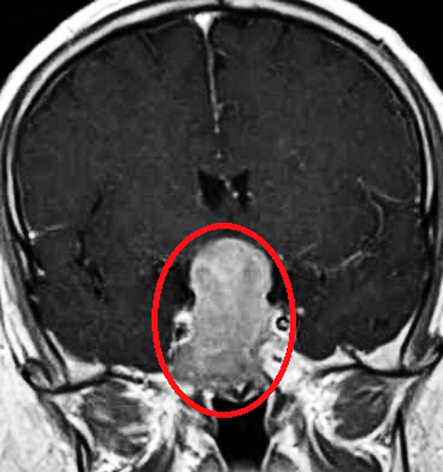

5. Imaging Features

• MRI (Magnetic Resonance Imaging): The primary imaging modality for pituitary adenomas.

• Microadenomas: Lesions less than 10mm in size, often visible on MRI.

• Macroadenomas: Larger tumors (greater than 10mm) that may extend into the cavernous sinus, causing compression of surrounding structures.

• Contrast Enhancement: Pituitary adenomas generally enhance with contrast due to their vascularity, though non-functional tumors may show less enhancement.